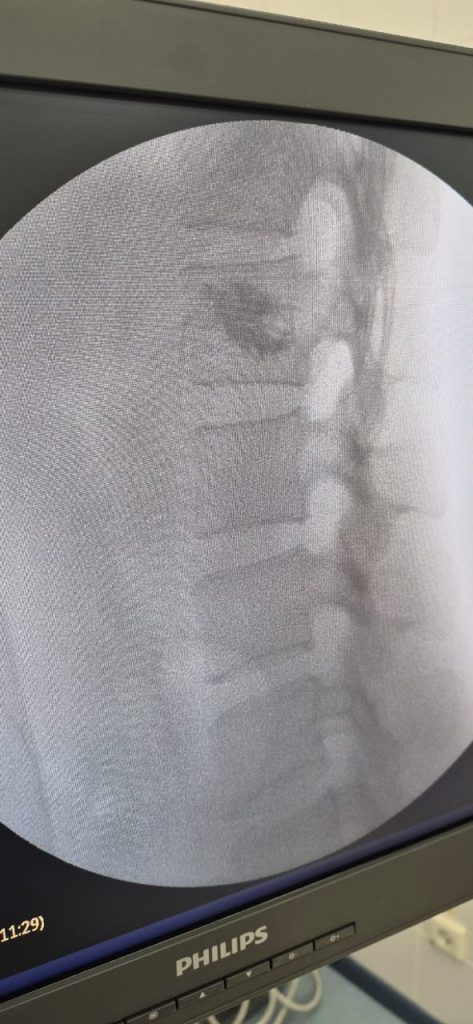

Бүгінде гемангиоманы емдеудің тиімді және қауіпсіз әдістерінің бірі — перкутандық вертебропластика. Бұл — теріге кішкентай тілік арқылы жасалатын кіші инвазивті процедура. Операция кезінде әлсіреген омыртқа денесіне арнайы медициналық цемент енгізіледі. Ол омыртқаны бекітіп, гемангиоманың өсуін тоқтатады және ауырсынуды жылдам басады. Процедура шамамен 20–30 минутқа созылады, жалпы жансыздандыру жасалады, ал науқас бірнеше сағаттан кейін-ақ өздігінен жүріп тұра алады.